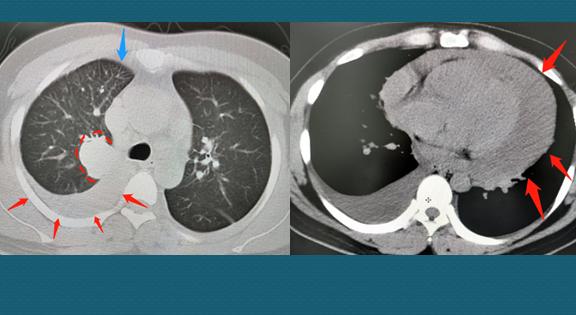

31岁,肺癌转移

才31岁,右肺3.8cm的肺癌,已经侵犯胸膜引起胸腔积液和心包积液,还有纵隔多发淋巴结转移和淋巴管癌,没有根治机会了。快过年了……